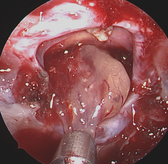

Das rein endoskopisch durchgeführte Verfahren macht sich die Nasenhaupthöhle sowie die Keilbeinhöhle als natürliche Zugänge zur vorderen Schädelbasis zunutze. In manchen Fällen muss der Zugang durch das Siebbein erweitert werden. Bei kleinen Prozessen reicht oft der Zugang durch nur eine Nasenhöhle. In diesen Fällen brauchen die Patienten nach der Operation auch keine Nasentamponade mehr.